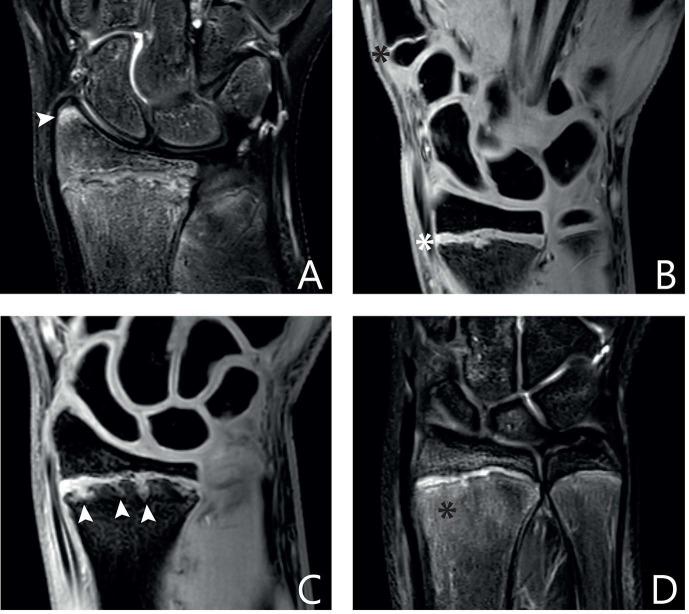

Twenty-four gymnasts with wrist pain, 18 asymptomatic gymnasts and 24 non-gymnastic controls (33 girls) underwent MRI of the wrist on a 3T scanner. Sequences included coronal proton density-weighted images with and without fat saturation, and three-dimensional water-selective cartilage scan and T2 Dixon series. Skeletal age was determined using hand radiographs. Three experienced musculoskeletal radiologists established a checklist of possible (peri)physeal abnormalities based on literature and clinical experience. Five other musculoskeletal radiologists and residents evaluated 30 MRI scans (10 from each group) using this checklist and reliability was determined using the intraclass correlation coefficient (ICC) and Fleiss' kappa. A final evaluation protocol was established containing only items with fair to excellent reliability.

Twenty-seven items were assessed for reliability. Intra-rater and inter-rater agreement was good to excellent (respective ICCs 0.60-0.91 and 0.60-0.78) for four epiphyseal bone marrow oedema-related items, physeal signal intensity, metaphyseal junction and depth of metaphyseal intrusions. For physeal thickness, thickness compared with proximal physis of first metacarpal, metaphyseal intrusions, physeal connection of intrusions and metaphyseal bone marrow signal intensity, intra-rater agreement was fair to excellent (ICC/kappa 0.55-0.85) and inter-rater agreement was fair (ICC/kappa 0.41-0.59). Twelve items were included in the final protocol.